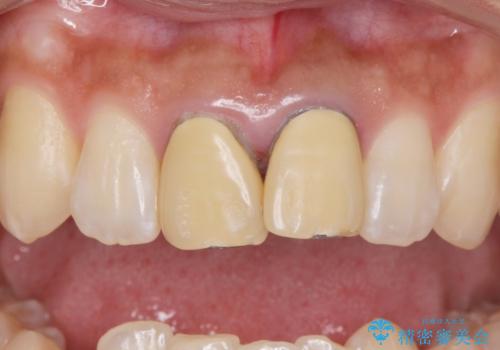

- 前歯のかぶせ物の変色を主訴に来院された患者様です。

根管治療からのやり直しはご希望されませんでした。

今回はe-maxクラウンで修復していきます。